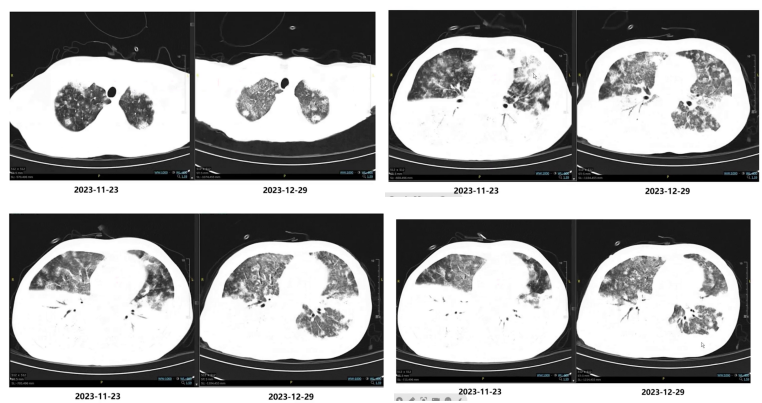

(3)随访影像学变化

(4)查体发现异常

2024-01-09予以第2周期PD-1单抗200mg,q3w抗肿瘤免疫治疗。后患者胸闷症状较前改善,Highflow仍高参数维持(温度37℃,氧浓度50%,流速50L/min),复查胸部CT后考虑肺内病灶较前部分吸收,患者病情总体相对稳定,予以出院。